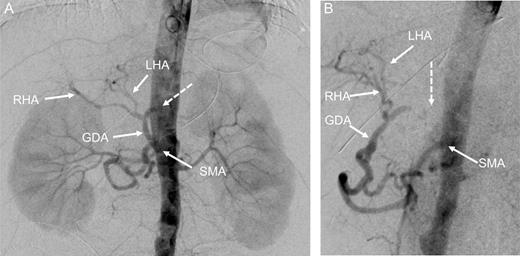

At this point, the patient was recommended for further investigation in the Interventional Radiological Department for both diagnosis confirmation and, most importantly, to provide an opportunity for stenting the celiac trunk. In order to accomplish this, gastro-duodenostomy, choledoco-choledocostomy (anastomosis between the resected common bile duct) and jejuno-jejunostomy re-anastomosis were performed, and a temporary abdominal closure was done. The patient was taken to the Radiological Department. CT and angiography (Figs 2 and 3) showed that there was a narrowing part of the celiac trunk, and distal to this part, there was an occlusion (high degree of stenosis) of the celiac artery. In addition, retrograde filling of the GDA could be appreciated through the patent SMA (Fig. 3). A stent was considered impossible due to the high degree of stenosis that was a nearly total occlusion of the celiac trunk.

Digital subtraction angiography (DSA) with pigtail catheter placed in the abdominal aorta: coronal (A) and 70° left anterior oblique (LAO) projections (B) demonstrating complete occlusion of the celiac trunk (dashed arrow). In addition, retrograde filling of the GDA can be appreciated through the patent SMA. RHA, right hepatic artery; LHA, left artery.